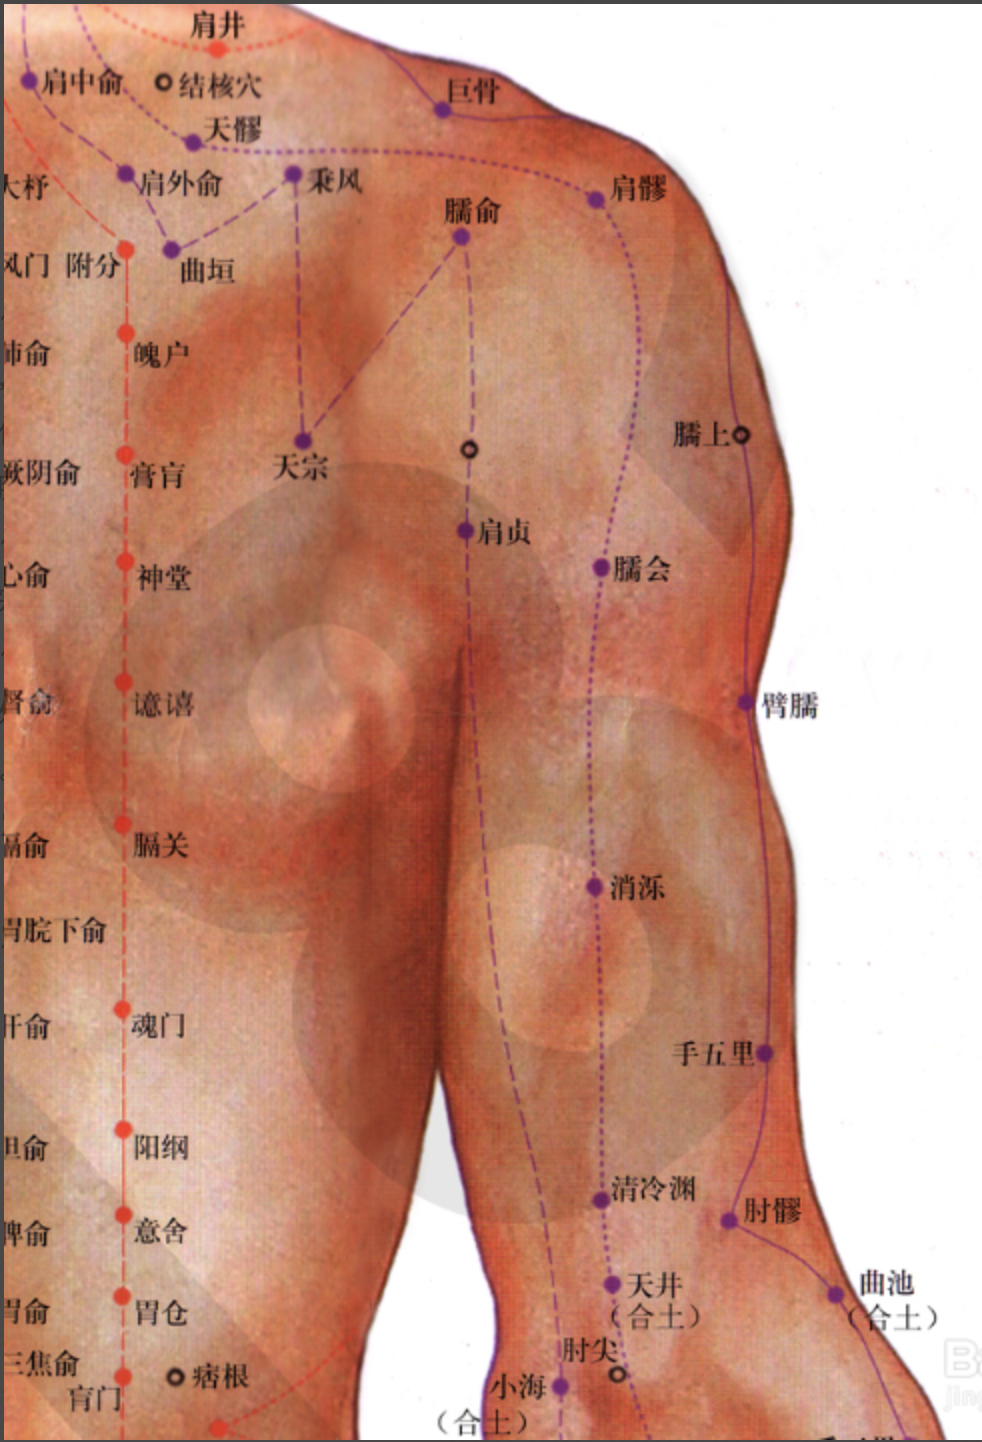

【(六)手太阳小肠经(图10-24-1)】

2、歌诀 手太阳经小肠穴,少则先行小指末,前谷后溪腕骨间,阳谷须同养老列,支正小海上肩贞,臑(nào)俞天宗秉风合,曲垣肩外复肩中,天窗循次上天容,此经穴数一十九,还有颧髎(liáo)入听宫。

3、经脉循行 起于手小指外侧端(少泽),沿手背外侧至腕部直上沿前臂外侧后缘,经尺骨鹰嘴与肱骨内上髁之间,出于肩关节,绕行肩胛部,交于大椎(督脉)向下入缺盆部联络心脏,沿食管过膈达胃,属于小肠。

缺盆部支脉:沿颈部上达面颊,至目外眦(zì),转入耳中(听宫)。

颊部支脉:上行目眶下,抵于鼻旁,至目内眦(睛明)、交于足太阳膀胱经。

4、主要病候 少腹痛、腰脊痛引睾丸、耳聋、目黄、颊肿、咽喉肿痛、肩臂外侧后缘痛等。

5、主治概要 主治头、项、耳、目、喉咽病、热病、神志病及经脉循行部位的其他病证。

天宗

【定位】 在肩胛部,当岗下窝中央凹陷处,与第 4 胸椎相平。

【主治】 肩胛疼痛,气喘,乳痈。

【配伍】 配肩外俞治肩胛痛,配膻中、足三里治乳痈。

【刺灸法】 直刺或斜刺 0.5 ~ 1 寸。

秉风

【定位】 在肩胛部,岗上窝中央,天宗直上,举臂有凹陷处。

【主治】 肩胛疼痛,上肢酸麻。

【配伍】 配天宗治肩胛疼痛。

【刺灸法】 直刺或斜刺 0.5 ~ 2 寸。

【附注】 手三阳与足少阳经交会穴。

【(七)足太阳膀胱经(图 10-25-1)】

2、歌诀 足太阳经六十七,精明目内红肉藏,攒竹眉冲与曲差,五处上寸半承光,通天络却玉枕昂,天柱后际大筋外,大杼(zhù)背部第二行,风门肺俞厥阴四,心俞督俞膈俞强,肝胆脾胃俱挨次。三焦肾气海大肠,关元小肠到膀胱,中膂(lǚ)白环仔细量,自从大杼至白环,各各节外寸半长,上髎次髎中复下,一空二空腰髁当,会阳阴尾骨外取,附分侠脊第三行,魄户膏肓与神堂。噫嘻膈关魂门九,阳纲意舍仍胃仓。肓门志室胞肓续,二十椎下秩边场,承扶臀横纹中央,殷门浮郗到委阳,委中合阳承筋是,承山飞扬踝附阳。昆仑仆参连申脉,金门京骨束骨忙,通谷至阴小指旁。

3、经脉循行 起于目内眦,上额交会于于巅顶(百会)。

风门

【定位】 在背部,当第 2 胸椎棘(jí)突下,旁开 1.5 寸。

【主治】 伤风,咳嗽,发热头痛,项强,胸背痛。

【配伍】 配肺俞、大椎治咳嗽、气喘,配合谷治伤风咳嗽。

【刺灸法】 斜刺 0.5 ~ 0.8 寸。

【附注】 足太阳经与督脉交会穴。

【(十)手少阳三焦经(图10-28)】

2、歌诀 二十三穴手少阳,关冲液门中渚旁。阳池外关支沟正,会宗三阳四渎长。天井清冷渊消泺(luò),臑会肩髎天髎堂。天牖(yǒu)翳风瘛(chì)脉青,颅息角孙丝竹空。和髎耳门听有常。

3、经脉循行 起于无名指末端(关冲)上行于第 4、5掌骨间,沿腕背、出于前臂外侧尺桡骨之间,经肘尖沿上臂外侧达肩部,交大椎,再向前入缺盆部,分布于胸中,络心包,过膈,从胸至腹,属于上、中、下三焦。

肩髎

【定位】 在肩部,肩髃(yú)后方,当臂外展时,于肩峰后下方呈现凹陷处。

【主治】 臂痛,肩重不能举。

【配伍】 配天宗、曲垣(yuán)治疗肩背疼痛;配肩井、天池、养老治上肢不遂、肩周炎。

【刺灸法】 直刺 0.5 ~ 1 寸;可灸。

肩井

【定位】 在肩上,前直乳中,当大椎与肩峰端连线的中点上。

【主治】 肩背痹痛,手臂不举,颈项强痛,乳痈,中风,瘰疬,难产,诸虚百损。

【配伍】 配足三里、阳陵泉治脚气酸痛,治疗乳腺炎特效穴。

【刺灸法】 直刺 0.5 ~ 0.8 寸,深部正当肺尖,慎不可深刺;可灸。

【附注】 足少阳、阳维之会。